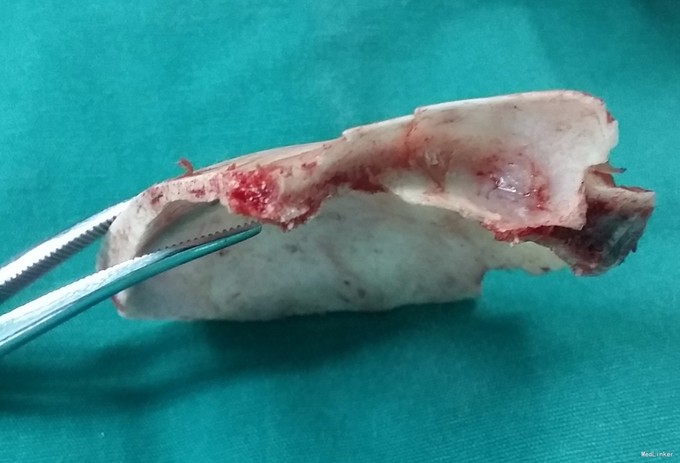

完善相关检查,在气管插管麻下行“左额眶部占位病变切除术”。术后病理诊断为“(左眼眶)丛状神经纤维瘤”。术后给予患儿脱水、营养脑神经、抗感染等对症治疗。复查CT未见明显异常。

患儿术后2周左眼睑下垂较术前好转。双侧瞳孔反射、眼球活动均无异常。 丛状神经纤维瘤主要发生于眼睑,在出生后或幼年时期即出现症状和体征。侵袭范围广泛,包括眼睑、眶内软组织、眶骨和邻近的脑、颞部等。眼部最早和最多见为上、下睑软性肥厚,皮下瘤组织增生,使上、下睑隆起。眼睑皮肤常有淡棕色色素斑,眼球向前突出和向下移位。眼球突出虽然很显著,但向眶内纳入并不困难。肿瘤组织可直接侵袭眶内各种结构,上睑提肌首先被波及,引起上睑下垂,上举不足或不能。MRI可准确显示病变的范围尤其显示病变与邻近结构的关系,也可清楚显示其他部位伴发的肿瘤,但难以清晰显示眶壁骨质改变。手术治疗是必要的,手术切除应注意以下问题:1.眼睑病变的切除;2.眶内病变的处理;3.提上睑肌的处理;4.眶骨缺失的处理。丛状型术前诊断容易,但治疗较为棘手,易复发。